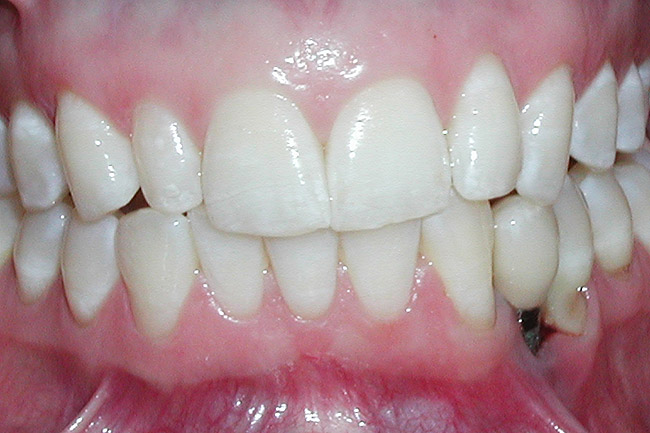

Figure 2  A preoperative retracted anterior view of the failing implant in the site of tooth No. 22.

Figure 2